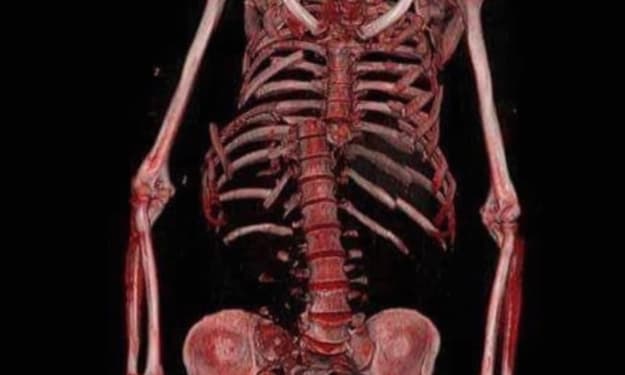

It wasn’t until day sixteen, when Lara began experiencing waves of nausea and dizzy spells, that she finally walked into an urgent care center. The attending physician took one look at her distended abdomen and ordered an abdominal X-ray.

The diagnosis: severe fecal impaction.